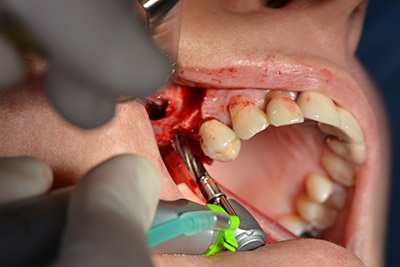

Sky implants (bredent) were used in this case. The surgical protocol of these, specify pilot drilling at about 1200 rpm (Fig. 9).

The following holes were drilled at a reduced speed of 300 rpm. The Implantmed demonstrated its true capability at this stage. The surgical protocol can be preset – the various positions can be selected simply by pressing the “P” position of the foot control (Fig. 10 to 11).

Inclined drilling

Image 10: Inclined drilling to dorso-cranial at 300 rpm.